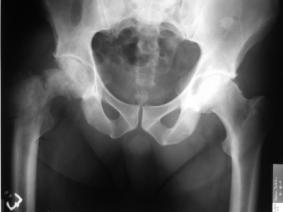

Csípőtáji törés:

A csípőtáji törések az osteoporosis legrettegettebb törései. Az életkor előrehaladtával elsősorban a hetvenedik év körül nő meg a jelentősége, mivel a csípőtáji törések ilyenkor válnak gyakoribbá. Az idősebb betegek eleve fogékonyabbak az őket érő erőbehatásokra és szervezetük emiatt sokkal érzékenyebben reagál egy hasonló mértékű traumára, mint korábban. Gyakrabban jöhetnek létre a törést követően sződmények. A leggondosabb orvosi ellátás mellett is egy éven belül minden ötödik betegünket elveszítjük. Magyarországon tíz évvel ezelőtt évente mintegy 8 ezer csipőtáji törés történt, napjainkban mintegy 14-15 ezer töréssel számolhatunk. Tehát az utóbbi tíz évben a csípőtáji törések száma megduplázódott.

Csípőtáji törést elszenvedett beteg Rtg felvétele